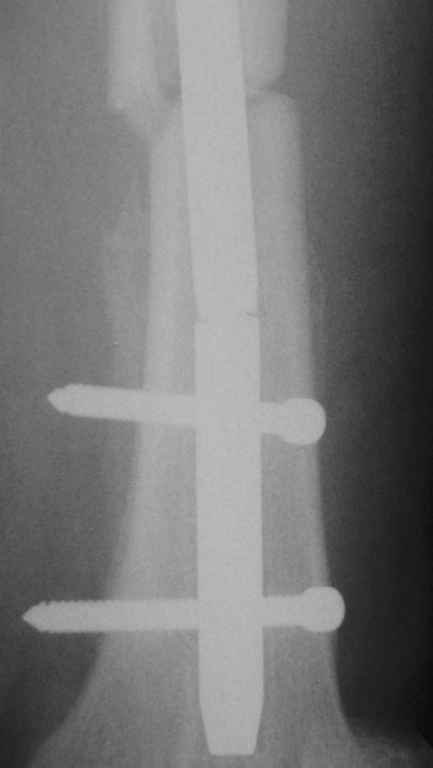

Перелом интрамедуллярного гвоздя

Уважаемые коллеги,Пациентка 40 лет, 6 мес назад был произведен интрамедуллярный синтез бедра канюлированным гвоздем без рассверливания. Обратилась в связи с появлением болей в бедре.

На Р-контроле – перелом гвоздя как следствие отсутствия динамизации конструкции (пациентка не обращалась в отделение). Планируем интрамедуллярный реостеосинтез с рассверливанием, однако возник вопрос о способе удаления дистального фрагмента гвоздя: с одной стороны – не хотелось бы беспокоить область перелома (разъединять отломки), с другой – лезть через колено-тоже не очень. Есть ли какие другие методы (удаления м/к) в данном случае?

1. сломанный стержень

2. проволока проведена точно в межмыщелковую ямку

3. в костномозговой канал введен новый стержень